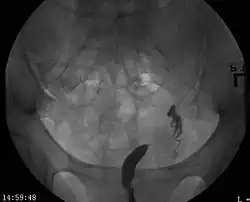

| A unicornuate uterus as seen on a hysterosalpingogram | |

A unicornuate uterus represents a uterine malformation where the uterus is formed from only one of the paired Müllerian ducts while the other Müllerian duct does not develop or only in a rudimentary fashion. The sometimes called hemi-uterus has a single horn linked to the ipsilateral fallopian tube that faces its ovary.[1]

Helpful techniques to investigate the uterine structure are transvaginal ultrasonography and sonohysterography, hysterosalpingography, MRI, and hysteroscopy. More recently 3-D ultrasonography has been advocated as an excellent non-invasive method to evaluate uterine malformations.[4]